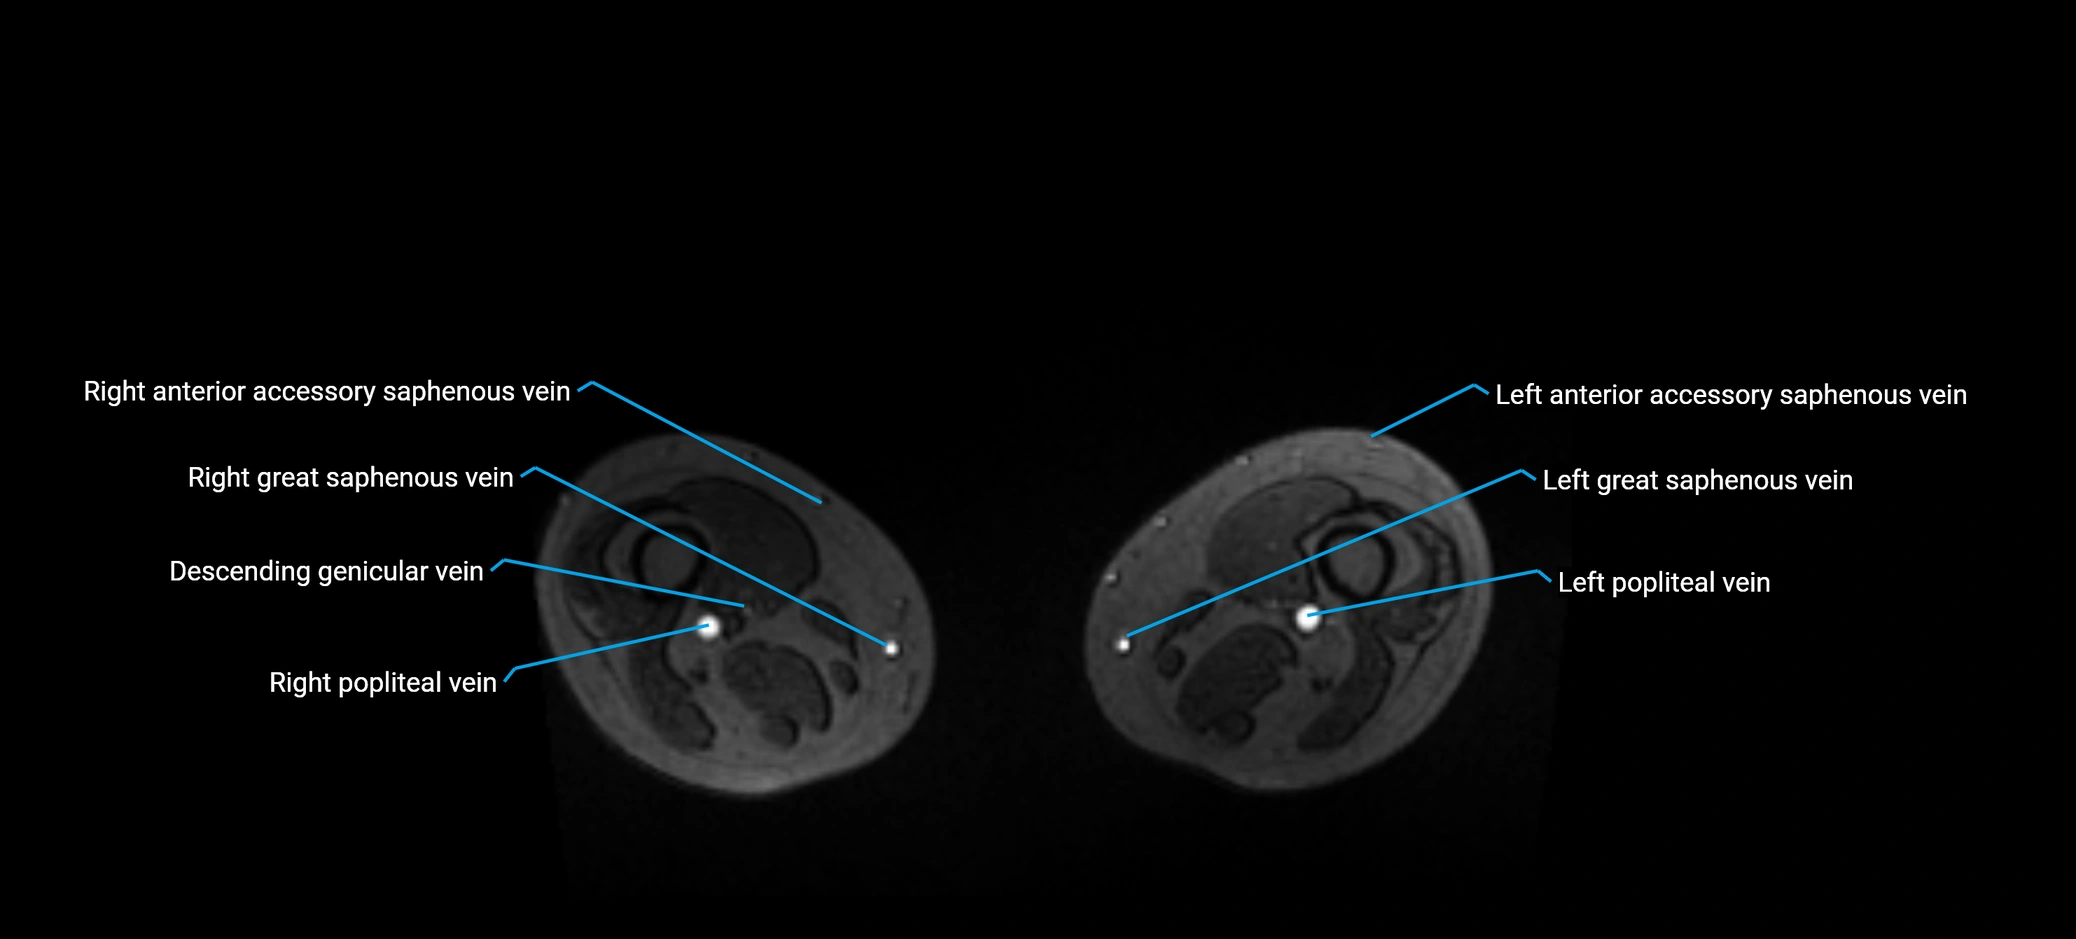

MRI image

image